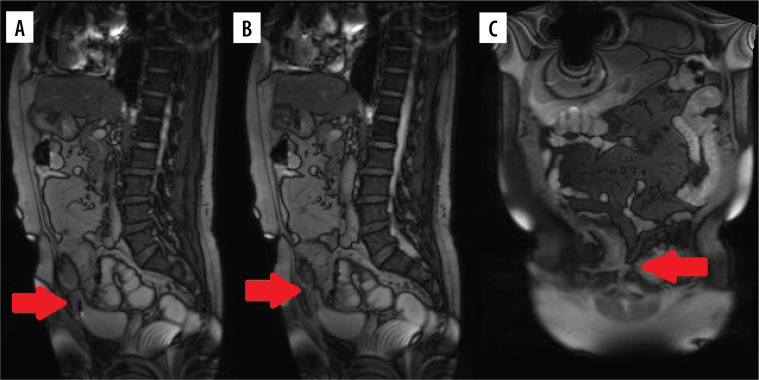

克罗恩病(CD)是临床上越来越常见的疾病。医学的进步延长了患者的生存时间,引入了新的治疗方法,以及疾病本身的性质意味着我们看到越来越多的新的,不寻常的这种疾病的并发症。我们回顾了三例罕见的乳糜泻并发症,重点讨论了影像学检查中可能出现的非典型并发症。乳糜泻及其治疗的并发症可发生在不同的器官和系统,并以非常非特异性的方式表现出来。如果不被注意,它们甚至可能危及生命;因此,在临床实践中,在评估CD患者时考虑其存在的可能性是很重要的。在评估这些人的影像学检查时,我们应考虑不典型体征和影像学特征的可能性,并考虑它们是否与潜在疾病有关。

Crohn's disease (CD) is an increasingly common disease in clinical practice. The progress of medicine, which has resulted in an extension of the survival time of patients, the introduction of new treatment methods, and the nature of the disease itself means that we are seeing more and more new, unusual complications of this disease. We have reviewed three cases of rare complications of CD, with a focus on possible atypical complications that may be seen on imaging studies. Complications of CD and its treatment can occur in various organs and systems, and manifest in very non-specific ways. If unnoticed, they can be even life-threatening; therefore, it is important in clinical practice to take into account the possibility of their presence when evaluating patients with CD. When assessing radiological examinations of these people, we should take into account the possibility of atypical signs and radiographic features, and consider whether they may be related to the underlying disease.